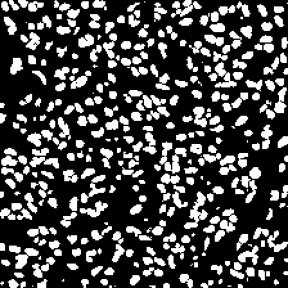

Microscopic image segmentation is a challenging task, wherein the objective is to assign semantic labels to each pixel in a given microscopic image. While convolutional neural networks (CNNs) form the foundation of many existing frameworks, they often struggle to explicitly capture long-range dependencies. Although transformers were initially devised to address this issue using self-attention, it has been proven that both local and global features are crucial for addressing diverse challenges in microscopic images, including variations in shape, size, appearance, and target region density. In this paper, we introduce SA2-Net, an attention-guided method that leverages multi-scale feature learning to effectively handle diverse structures within microscopic images. Specifically, we propose scale-aware attention (SA2) module designed to capture inherent variations in scales and shapes of microscopic regions, such as cells, for accurate segmentation. This module incorporates local attention at each level of multi-stage features, as well as global attention across multiple resolutions. Furthermore, we address the issue of blurred region boundaries (e.g., cell boundaries) by introducing a novel upsampling strategy called the Adaptive Up-Attention (AuA) module. This module enhances the discriminative ability for improved localization of microscopic regions using an explicit attention mechanism. Extensive experiments on five challenging datasets demonstrate the benefits of our SA2-Net model. Our source code is publicly available at \url{https://github.com/mustansarfiaz/SA2-Net}.